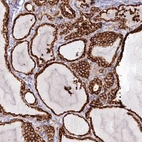

Immunohistochemical staining of human thyroid gland shows strong cytoplasmic positivity in glandular cells.